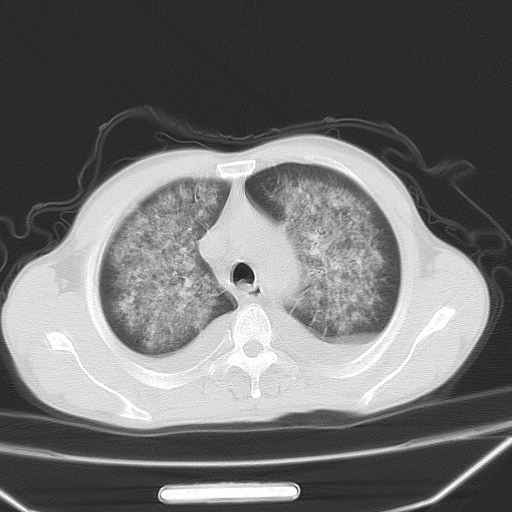

男、42岁、咯血3天。既往有甲亢、贫血、血尿蛋白尿史多年。血象:wbc:6.   中性粒:70.6%。

双肺野对称性磨玻璃影,分布于内中带,双侧胸水,患者有咯血。

1、间质性肺水肿;2、结合临床病史及实验室检查,考虑为肺出血肾炎综合征。    此病需与间质性炎症、粟粒性肺结核鉴别。

肺出血-肾炎综合征又称good-pasture综合征,属少见病,近几年国内有散在报告。此病原因未明,目前多数学者认为与自身免疫有关,即病人体内存在抗-gbm抗体,而病人肺毛细血管基底膜与肾小球基底膜有交叉反应性抗原,从而引起肺泡毛细血管基底膜和肾小球基底膜病变,导致肺出血及肾炎表现。血清抗-gbm抗体阳性,或组织活检见沿肾小球和肺泡基底膜有igg沉积,为本病的3个诊断依据。临床上有许多疾病同时表现为肺出血和肾炎,如系统性红斑狼疮、韦格肉芽肿和增殖性肾小球肾炎等,但这些疾病都不同时具备上述三方面的条件